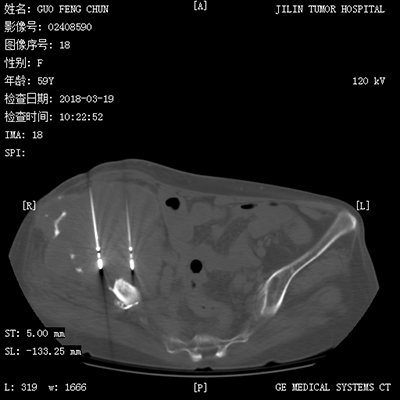

(肺癌的介入治療)(盆腔惡性腫瘤的介入治療)

(骨惡性腫瘤的消融治療) (CT引導(dǎo)下骨水泥注射椎體成形術(shù)及粒子植入術(shù))